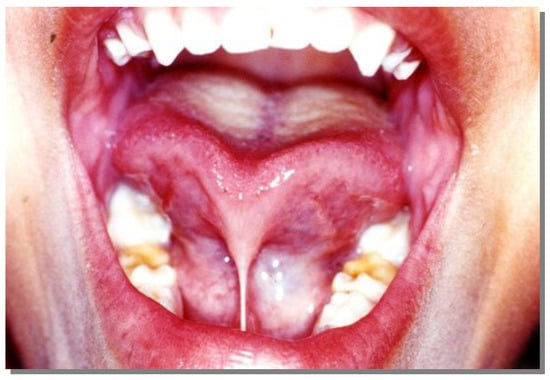

Clinically, when the lingual frenum is short, the tongue has a ‘V’ notch when elevated or stretched outside the buccal cavity and only the lateral part of the tongue has some mobility. Figure 1 demonstrates the clinical aspect of this condition.

Figure 1.

Clinical aspect of ankyloglossia.

Maximum tongue protrusion. Note the “V” notch at the anterior region.

Figure 10.